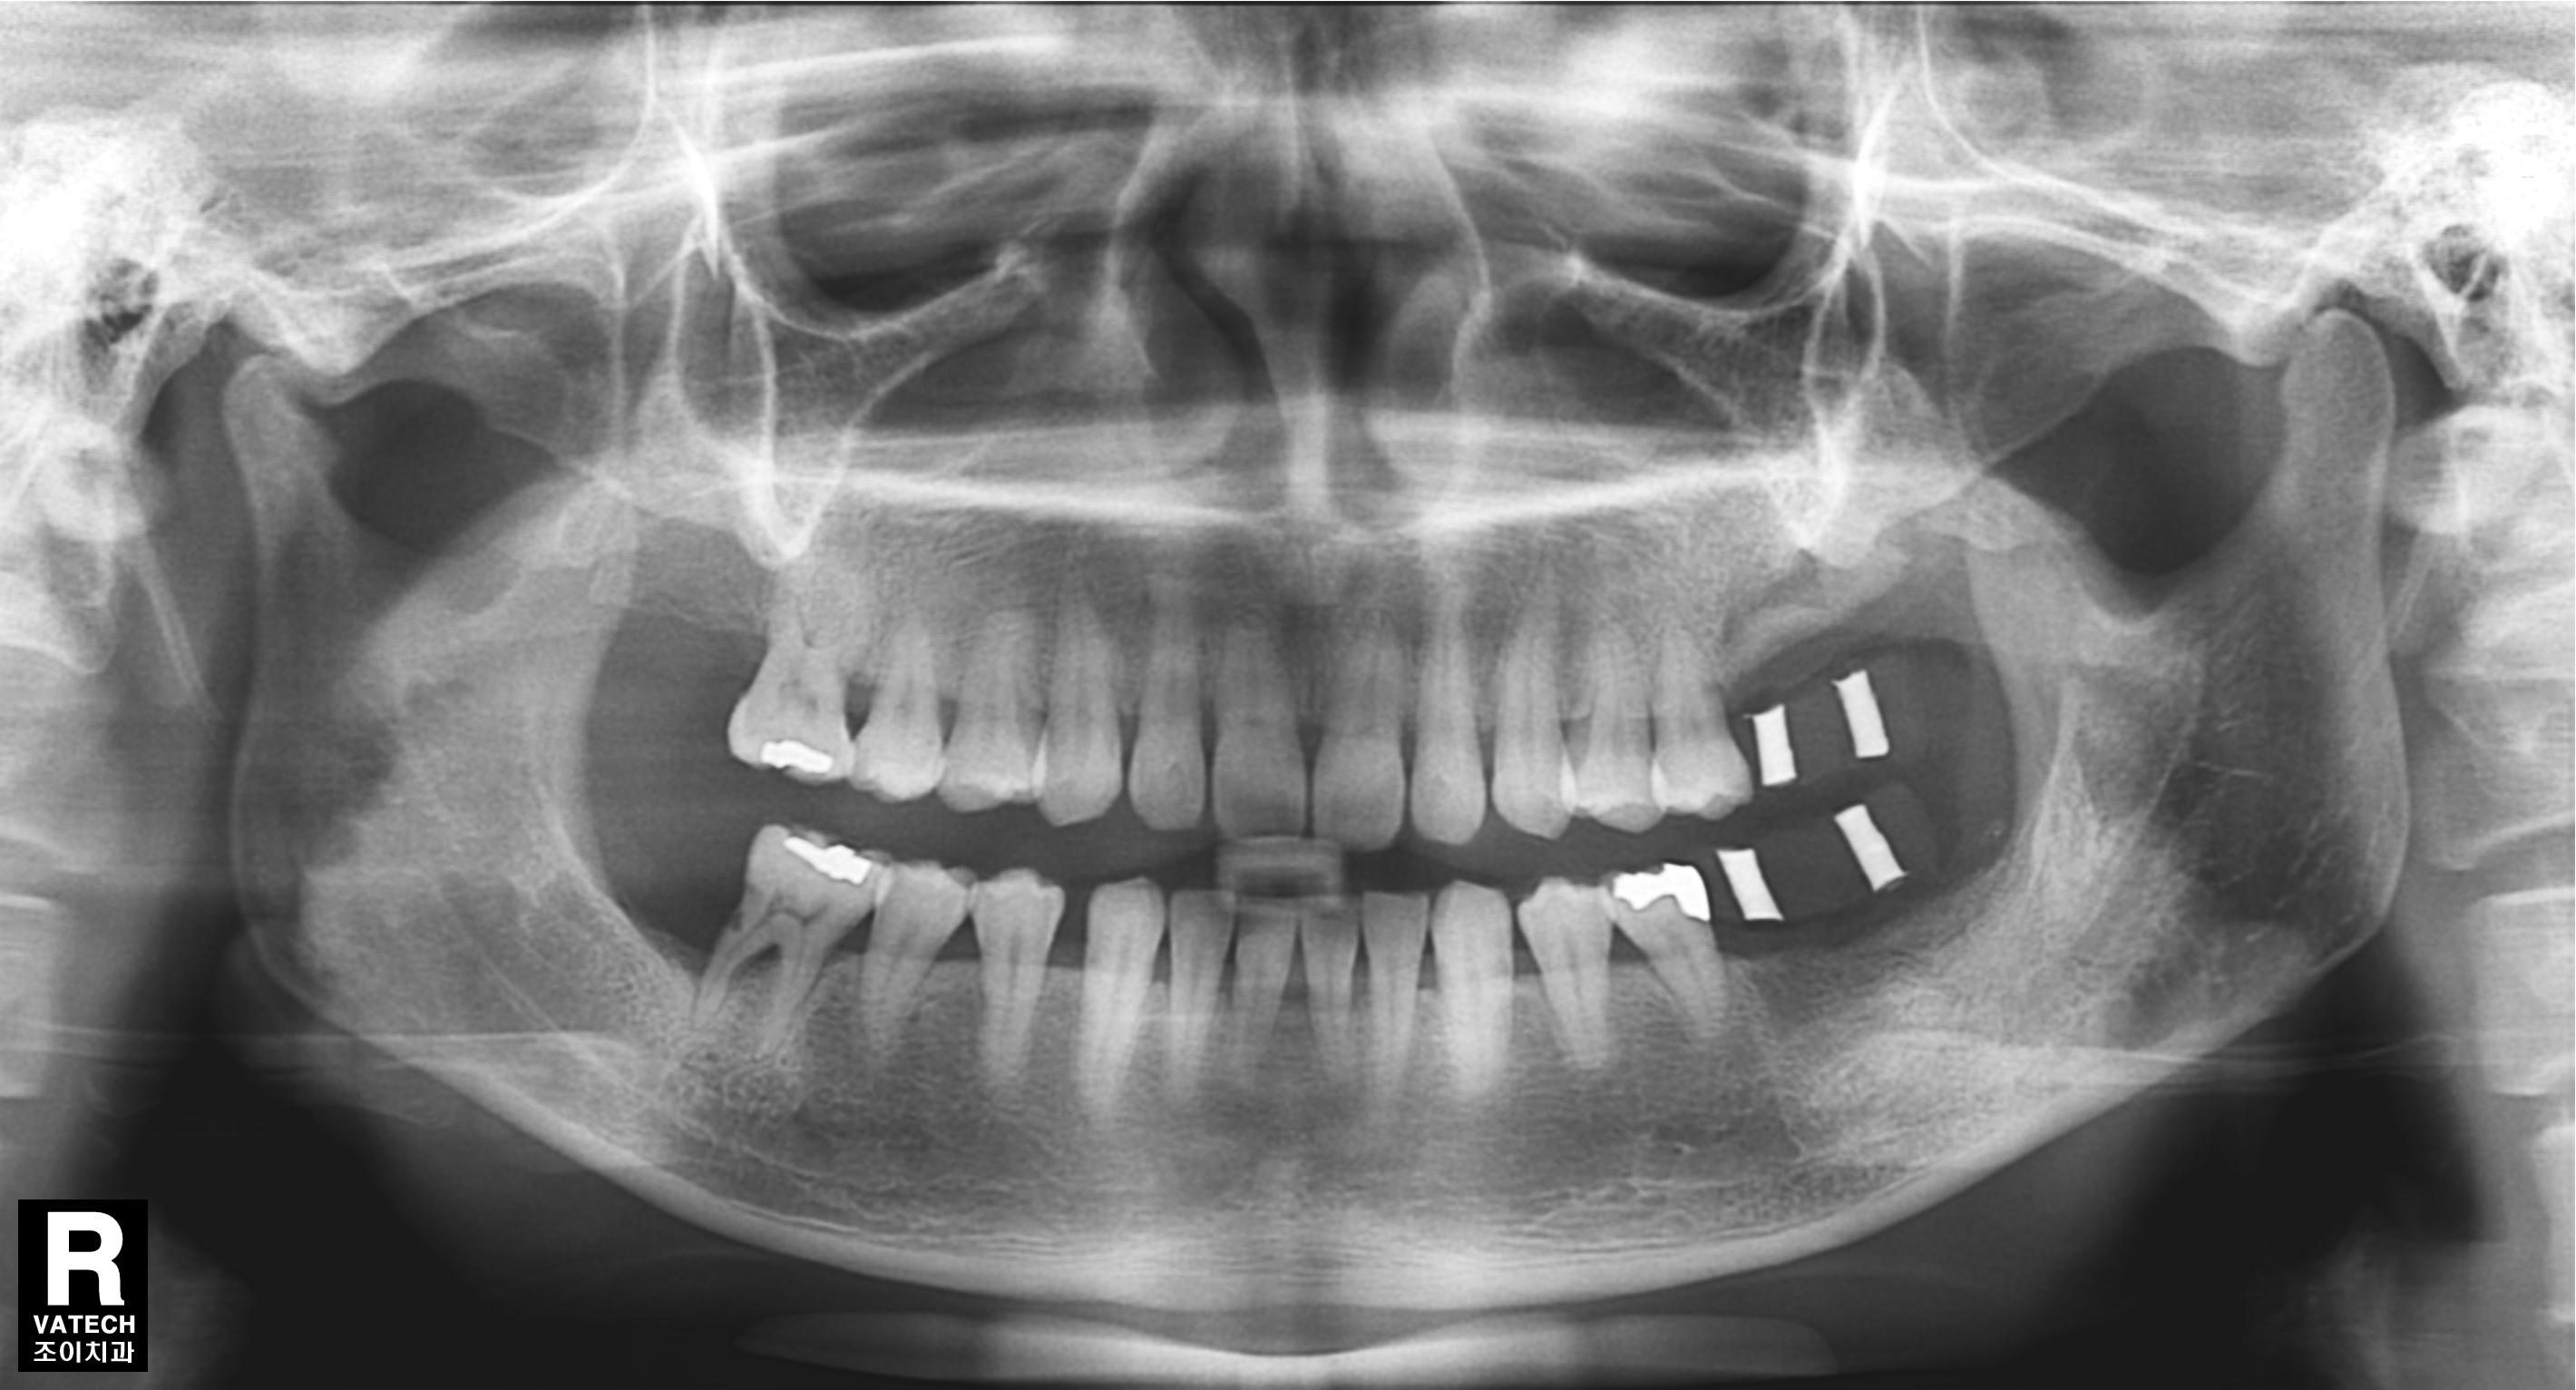

[임플란트] 제목 : 잇몸뼈가 심하게 녹은 환자에서의 임플란트

치주질환으로 치조골이 많이 녹아 내려간 경우 원하는 위치에 바로 임플란트를 심을 수 없는 경우가 많습니다.

또한 임플란트의 실패율도 높아집니다.

이 경우 골을 이식하는 것을 먼저 하고 수개월이 경과한 후에 다시 임플란트를 심어야 합니다.

그래야 원하는 위치에 임플란트를 심을 수 있고, 성공율을 높이며, 장기간 문제 없이 잘 유지할 수 있습니다.